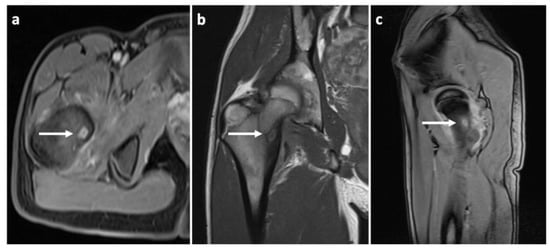

Figure 3.

Different MRI (magnetic resonance imaging) views with white arrows indicating the location of the osteoid osteoma. (a) T1 vibe dixon transverse projection; (b) T1 TSE (turbo spin echo sequence) frontal projection; (c) T1 vibe dixon sagittal projection.

To prove the diagnosis of OO, a CT scan of the affected area was taken. The condition was consulted with a neurologist, who found decreased reflexivity in the L2–L4 myotomes, and, therefore, recommended a lumbar spine MRI to rule out any spinal lesions (e.g., a tumor). No such affection was found. Even though our diagnostic algorithm was not standard (among other things, due to the fact that the patient was referred to our workplace only after the MRI was performed), we arranged the individual diagnostic steps and the Figure 1, Figure 2 and Figure 3 (i.e., clinical examination–CT–MRI) in the correct order for better clarity.